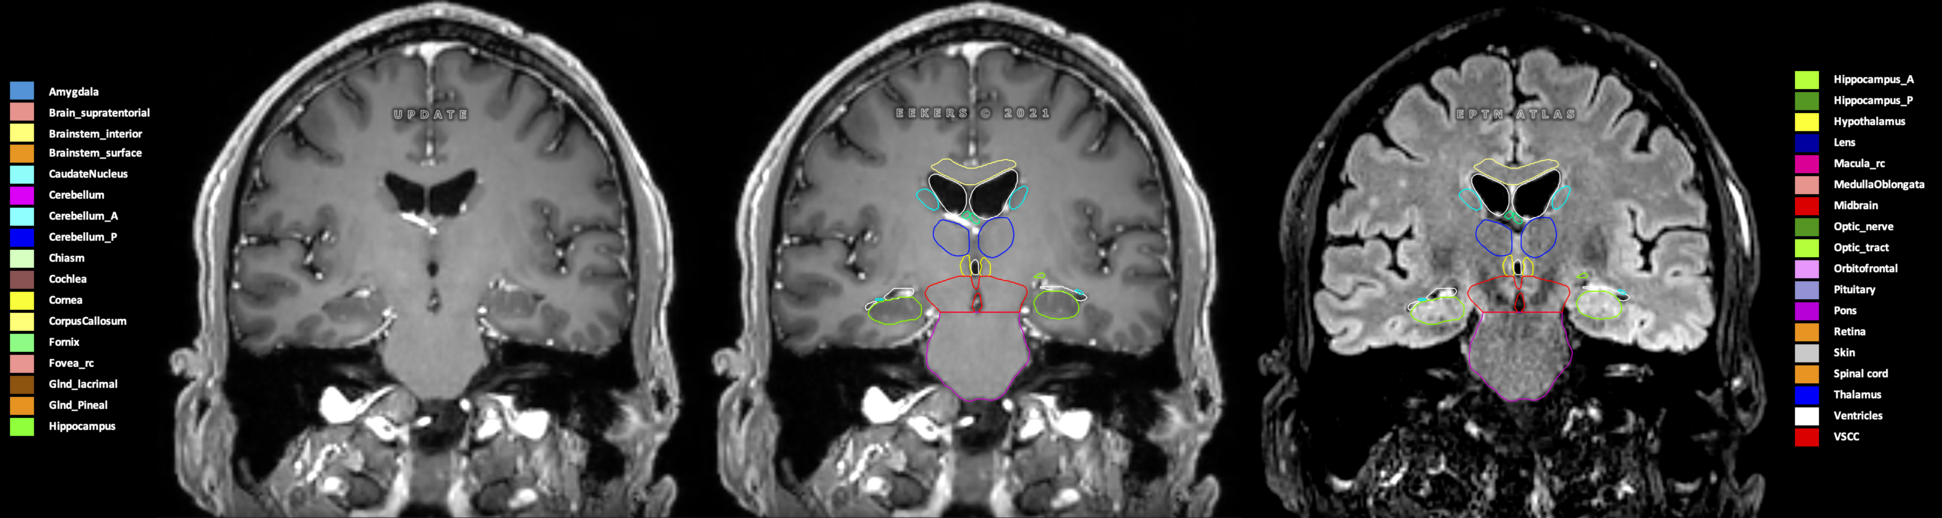

Eekers et al. have published an international neurological atlas for contouring of organs at risk in consensus with the European Particle Therapy Network (EPTN) in 2018 and an update in 2021. The purpose of this consensus atlas is to decrease inter- and intra-observer variability in delineating OARs relevant for neuro-oncology.

Included are all OARs known to be relevant for radiation-induced toxicity in neuro-oncology: brain, brainstem (midbrain, pons, medulla oblongata), chiasm, cerebellum (anterior & posterior), cochlea, cornea, hippocampus (anterior & posterior), hypothalamus, lens, lacrimal gland, optic nerve, pituitary, skin, and vestibular & semicircular canals. To further facilitate research on cognition, vision and radiological changes after irradiation of the brain, potential clinically-relevant OARs are included: amygdala, caudate nucleus, cerebellum (anterior & posterior), corpus callosum, fornix, macula, optic tract, orbitofrontal cortex, periventricular space (PVS), pineal gland, and thalamus.

Three-dimensional delineation of the 25 consensus OARs for neuro-oncology are shown on CT (WW/WL 120/40, 3000/600), 3T MR images, (T1Gd, T2FLAIR 1mm) and 7T MR (MP2RAGE 0.7 mm). All are presented in transversal, sagittal and coronal view.